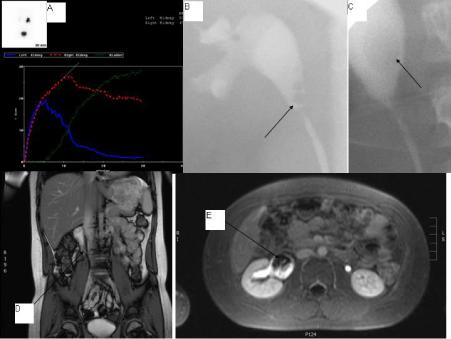

Ureteric Fibroepithelial Polyp in a Child-Recurrent Presentations and Diagnostic Dilemma Open Access

Ureteric Fibroepithelial Polyp in a Child-Recurrent Presentations and Diagnostic Dilemma

Swamy KB, Govani DR, Mehta AR, et al.

Benign ureteral polyps, also known as fibroepithelial polyps, can cause upper urinary tract obstruction by growing to block the flow of urine from the kidney. Fibroepithelial polyps are very rare benign lesions originating from the mesoderm. We have presented an interesting and unusual case who…...